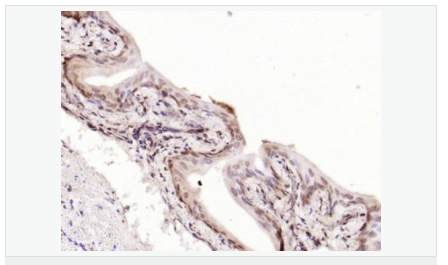

產品應用WB=1:500-2000 ELISA=1:5000-10000 IHC-P=1:100-500 IHC-F=1:100-500 Flow-Cyt=1μg /test IF=1:100-500 (石蠟切片需做抗原修復)